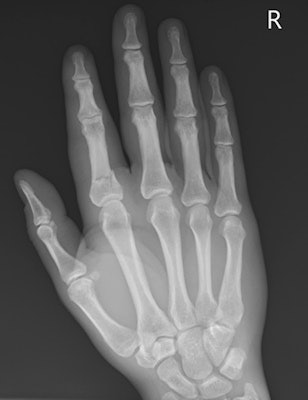

"Approximately 250 persons attend the emergency department per year with various hurling-related injuries, mostly young adults, particularly during the peak season and school matches. Hand, wrist, and upper limb injuries are the commonest," noted Dr. Nagabathula Ramesh, from the department of radiology at Midland Regional Hospital in Portlaoise, Republic of Ireland.

The most common cause of injuries is when a player is tackled by another player, and the injuries range from simple bruising and abrasions to severe dislocations and multiple system trauma. Upper extremity trauma tends to be more common in hurling, particularly the hand and the wrist, while orbital and facial are common in both types of sports, Ramesh explained.